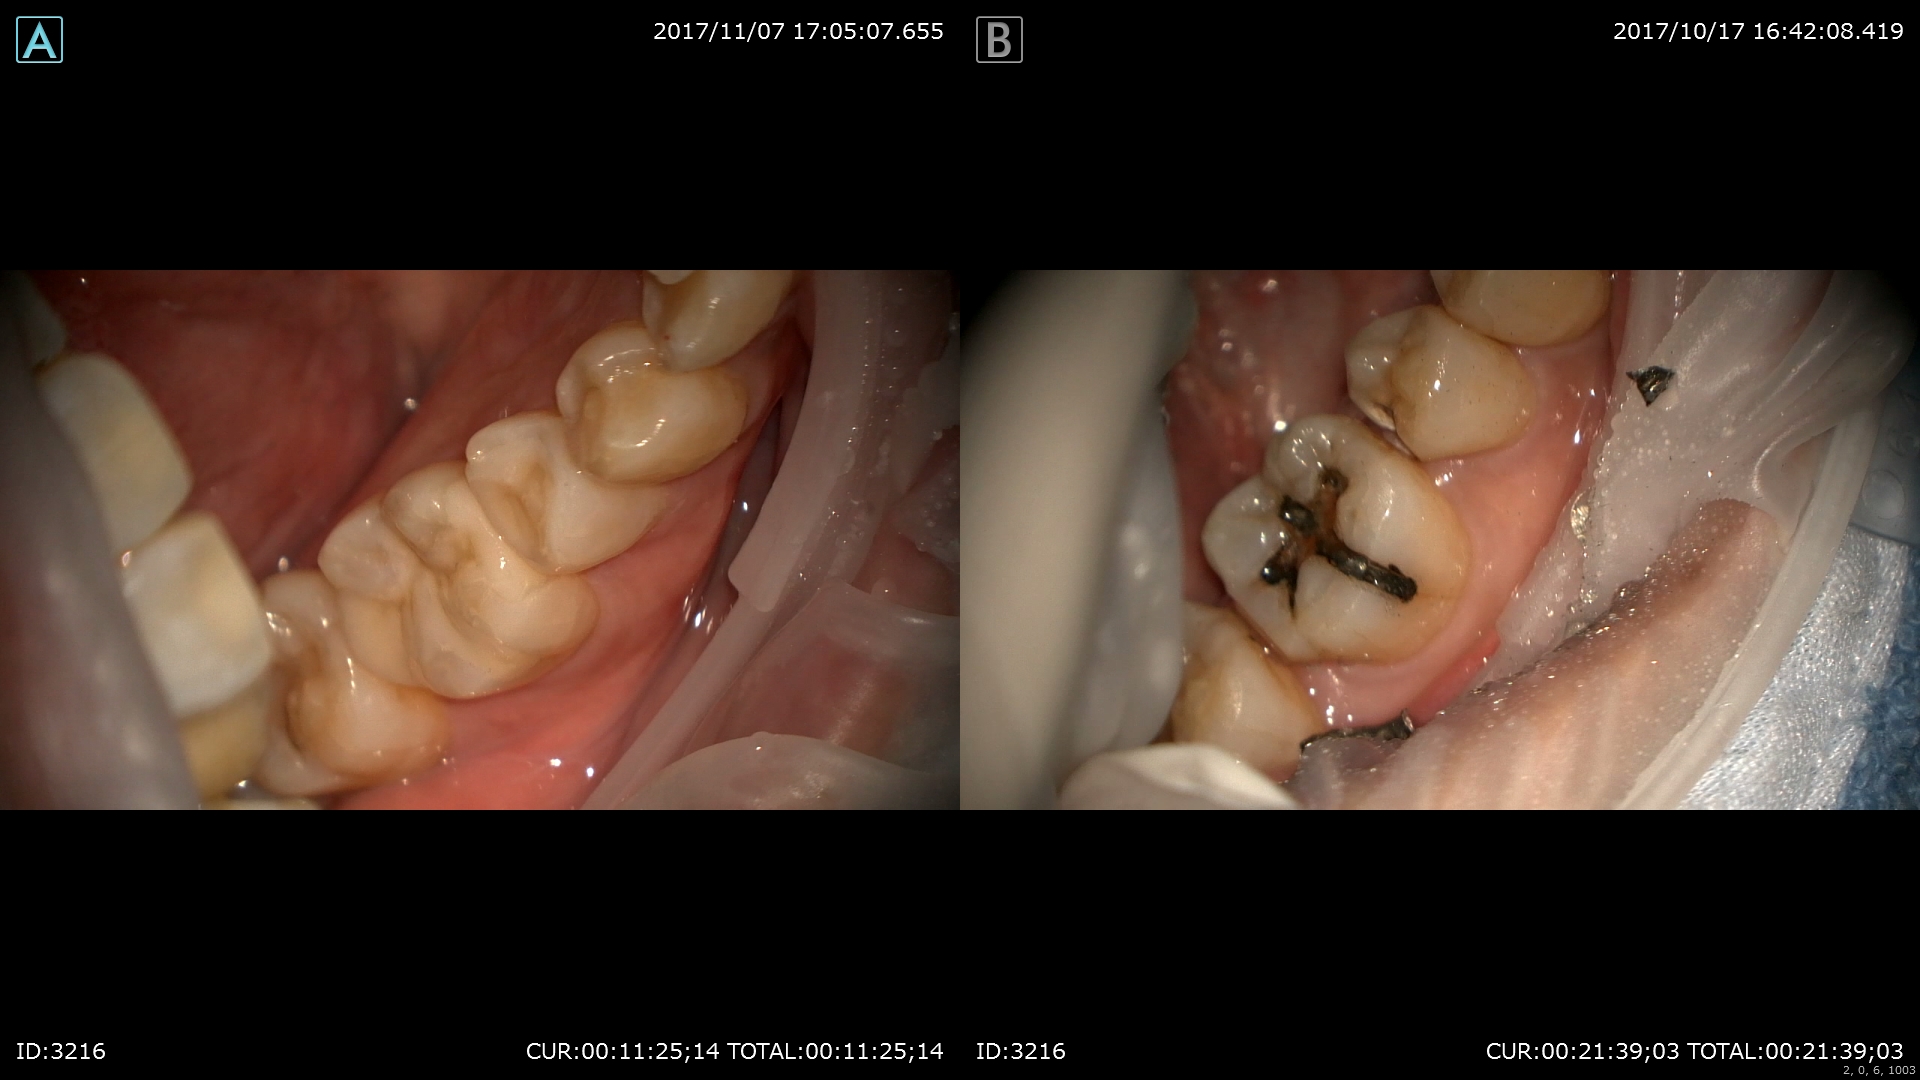

神経保護を行いました。

本日修復終了

術前(右)術後(左)